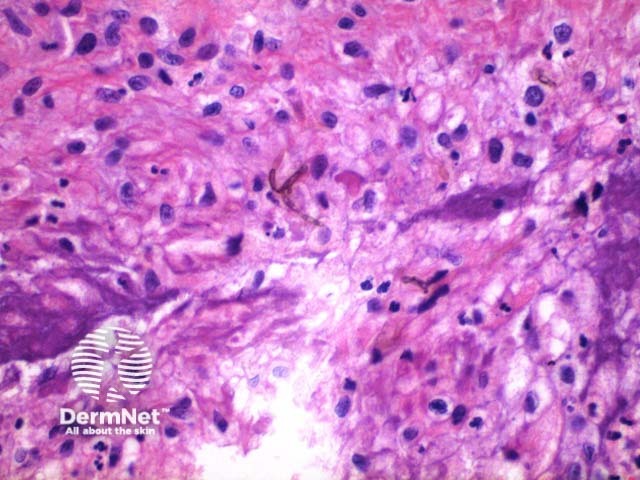

Scanning power view of phaeohyphomycosis shows a deeply extending granulomatous pattern (Figure 1) which may show areas of necrosis (Figure 2). Centrally an abscess or cystic nodule may form. Frequently a foreign body such as a wood splinter can be seen. The epidermis commonly shows pseudoepitheliomatous hyperplasia. The inflammatory infiltrate is comprised of histiocytes with multinucleated giant cells, and numerous neutrophils (Figures 3,4 and 5). At high power branching septate pigmented fungal hyphae can be seen (Figure 6).

Figure 3